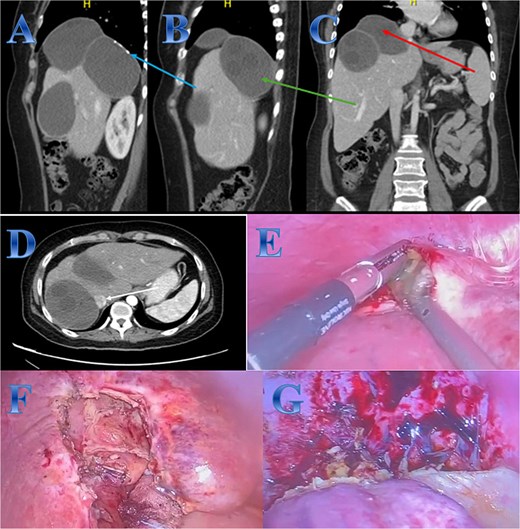

Case 4

A 31-year-old male presented with a 5-days history of epigastric pain accompanied by jaundice, darkened urine, together with a clay stool. On examination, there was jaundice with epigastric tenderness. Clinical tests showed increased total and direct bilirubin levels. CT showed left hepatic lobe exophytic CE (Fig. 4).

Case 4. (A & B) Post-contrast CT cuts showing well-defined cystic lesion showing internal daughter cysts noted at the left hepatic lobe and seen exophytic indenting the lesser curvature of the stomach, septate lesion is seen in the left lobe of the liver (photo A). The lesion is abutting the lesser curvature of the stomach with intact fat planes between the two (photo A). (C & D) MRI cuts showing well-defined, septate lesion, abutting the lesser curvature of the stomach. The lesion makes some mass effect off the left hepatic biliary radicles communicating with the lesion (photo C).

The patient underwent ERCP for biliary drainage. Subsequent follow-up revealed improved jaundice and reduced pain; at that time, the patient was started on albendazole, which continued for 2 months. The patient was admitted for surgery, and laparoscopic left lateral resection was done. After liver mobilization was done by detaching the falciform, left triangular and coronary ligaments to mobilize the left liver lobe. Retraction of the left lateral segment was performed to expose segments 2 and 3 which were isolated using laparoscopic gauze soaked in hypertonic saline A harmonic scalpel was used for parenchyma transection, and the left bile duct was identified between segments 4 and 2 and 3, which was transected using endovascular gastrointestinal stabler (endo-GIA). Before ending the parenchyma dissection upward, the left hepatic vein was identified and divided using endo-GIA (Fig. 4).